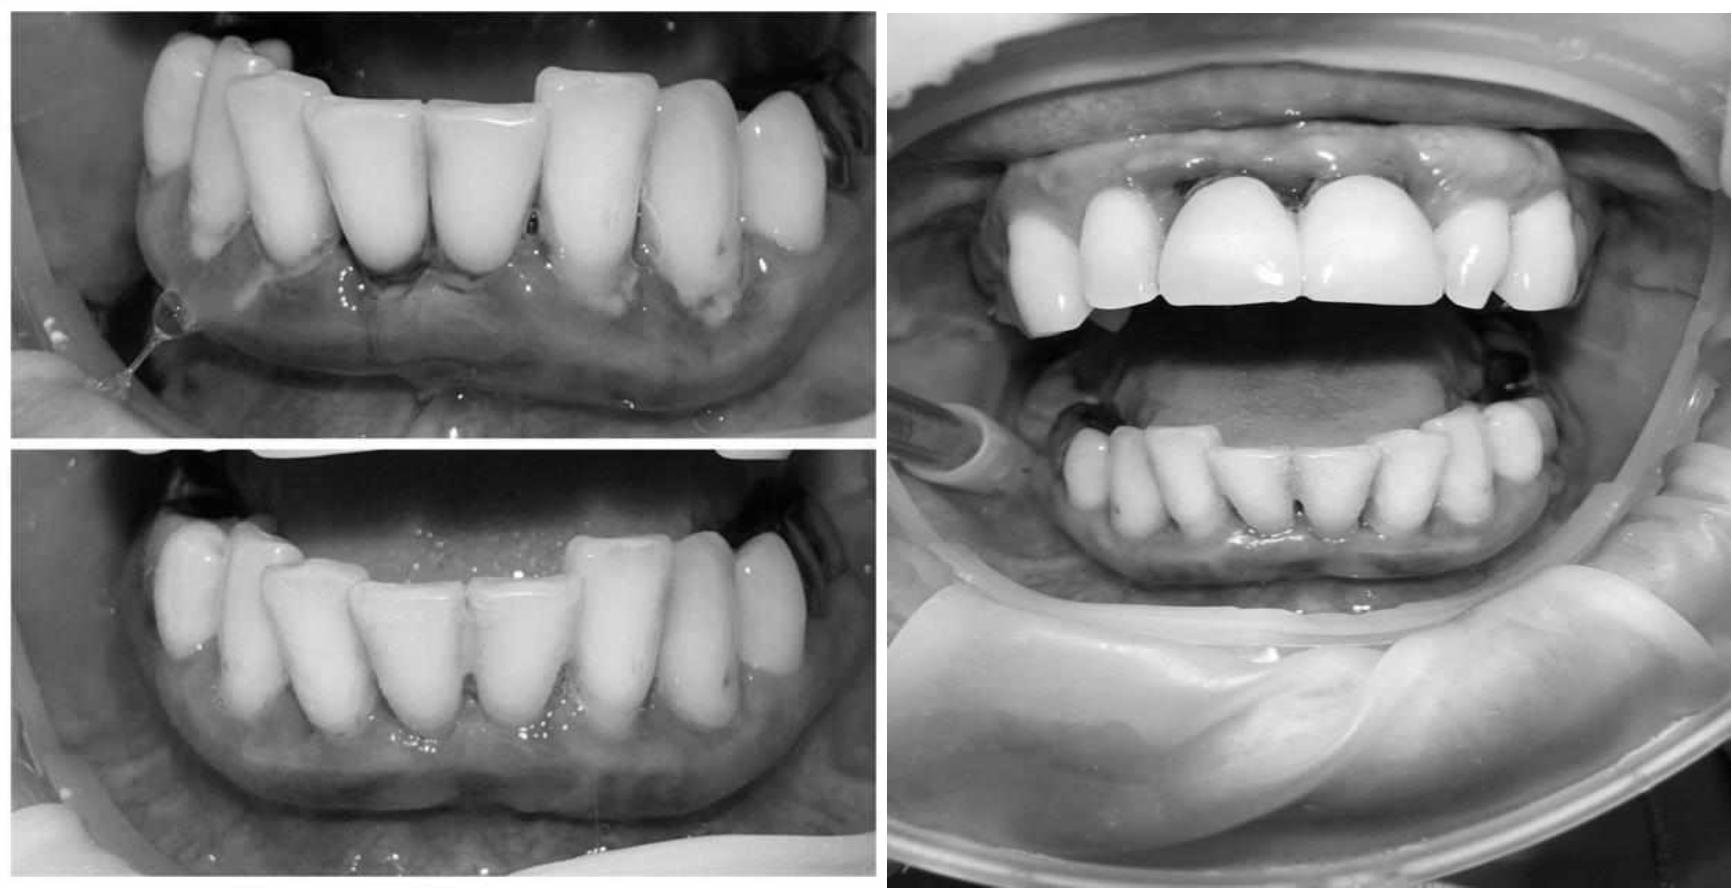

Ранее у пародонтолога не наблюдалась. При осмотре выявлены: неудовлетворительная индивидуальная гигиена полости рта, пародонтальные карманы до 7 мм, обильная кровоточивость и гноетечение из пародонтальных карманов, подвижность зубов 4.2, 4.1, 3.1, 3.2 II степени, обильные над- и поддесневые зубные отложения (рис. 1). На ортопантомограме отмечается резорбция костной ткани до ½ длины корня, очаги остеопороза (рис. 2). Пациенту был поставлен диагноз хронический генерализованный пародонтит тяжелой степени тяжести. При осмотре была составлена пародонтограмма с использованием компьютерного зондирования (рис. 3).

Через 6 месяцев при осмотре выявлен удовлетворительный уровень индивидуальной гигиены, отсутствие участков кровоточивости и гноетечения (рис. 4), пародонтальные карманы уменьшились в размерах (рис. 5). Пациент отмечает значительные улучшения. После стабилизации пародонтологического статуса пациент направлен для дальнейшего ортопедического лечения.

Рис. 4. Динамика результата через 6 месяцев

Рис. 5. Пародонтограмма с использованием компьютерного зондирования через 6 месяцев